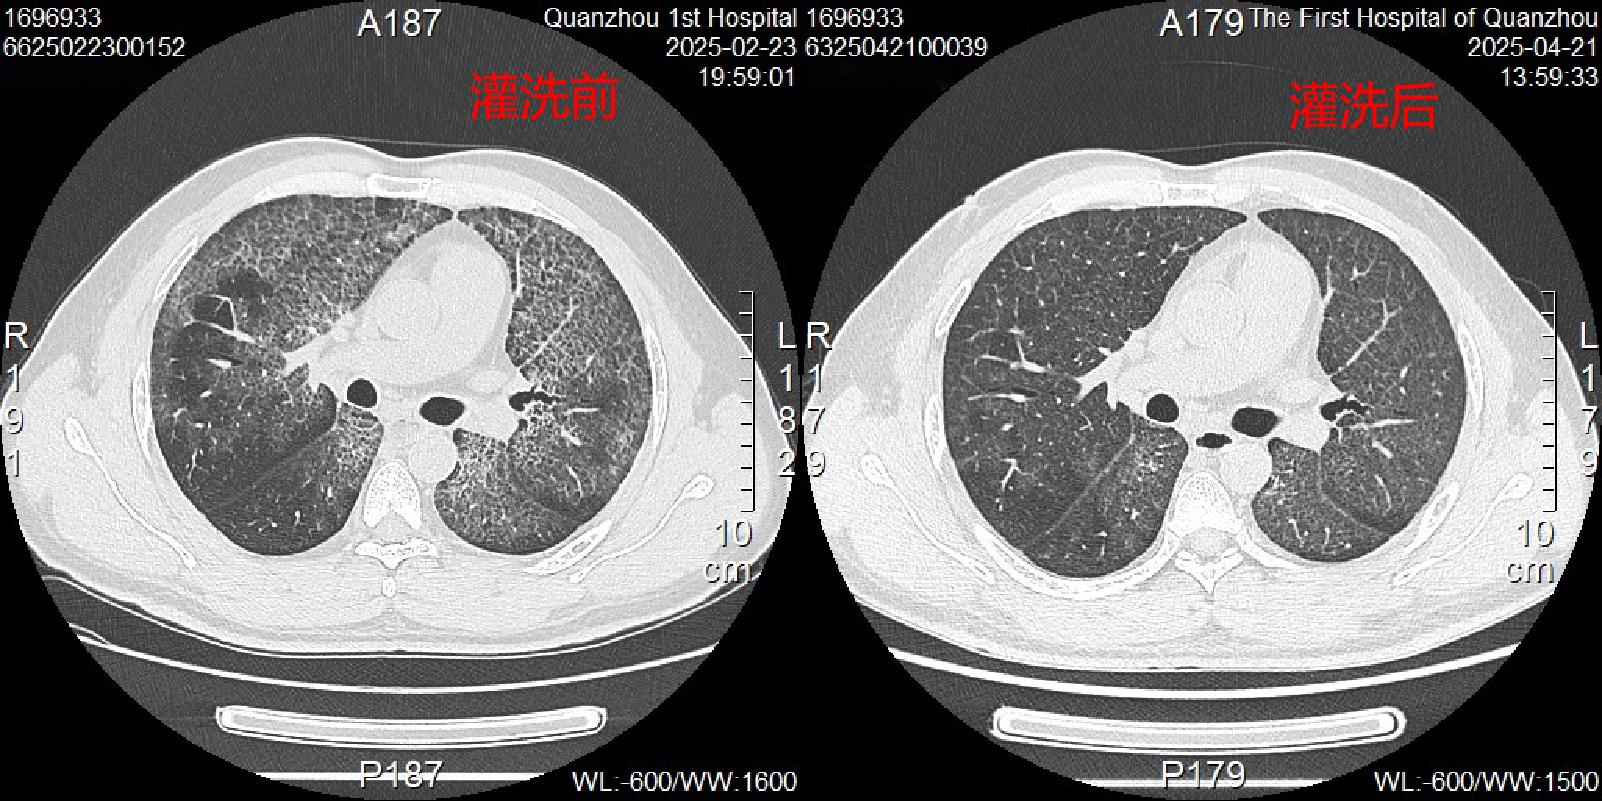

術前患者胸部CT顯示兩個大白肺

經(jīng)過雙肺分期全肺灌洗后,傅先生的呼吸困難癥狀好轉(zhuǎn),活動耐力提高,復查胸部CT顯示雙肺磨玻璃影明顯減少、肺彌散功能較前好轉(zhuǎn),順利出院。